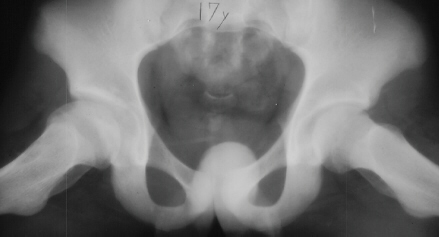

11 yrs 3 mos, , 12 yrs, 13 yrs 8 mos , 17 yrs , 18 yrs.